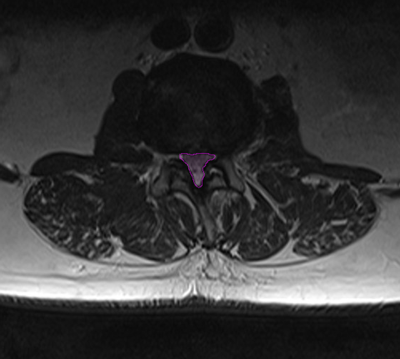

Φυσιολογικός ευρύς σπονδυλικός σωλήνας αριστερά (πράσινο) με άφθονο χώρο γύρω από τα νεύρα (βέλος). Στενός σπονδυλικός σωλήνας δεξιά με συμπίεση των νεύρων. |